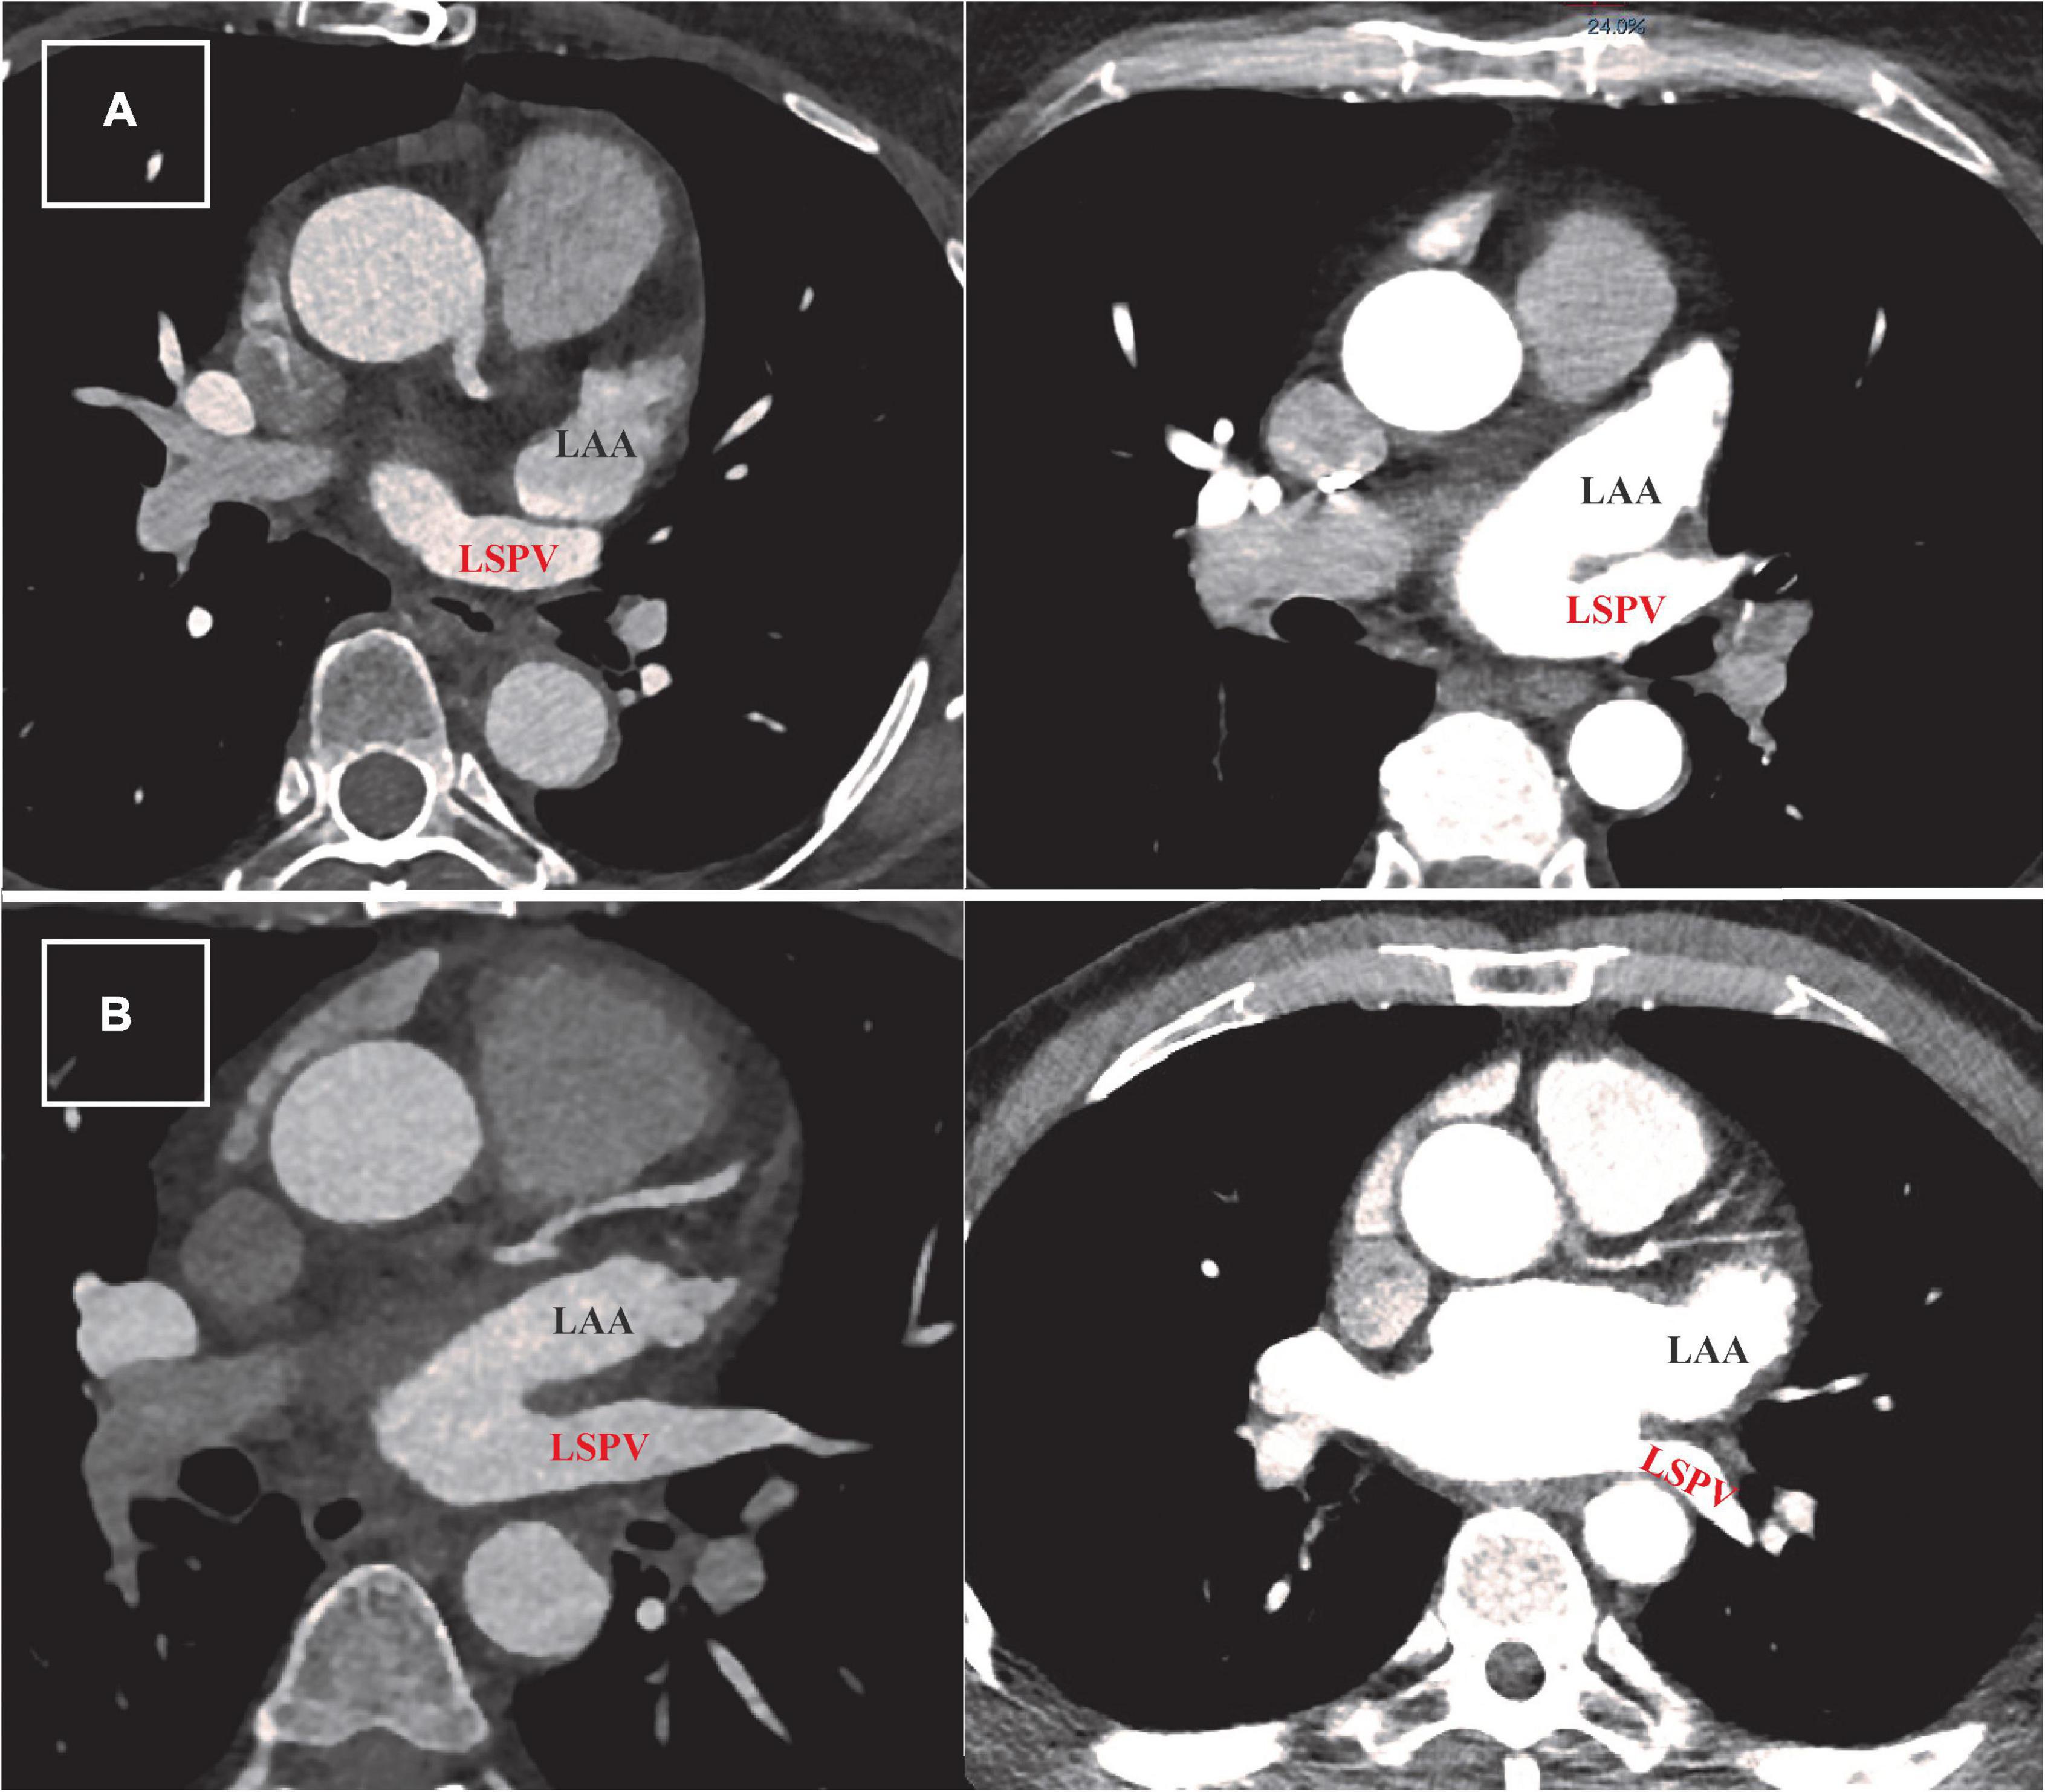

Our standard scan acquisition protocol consists of a high-pitch acquisition in the arterial phase covering at least the LA and a delayed phase high-pitch acquisition of at least the LAA. CT angiography examinations were performed with a 384-slice scanner (SIEMENS SOMATOM Force, Siemens Healthlineers) with prospective electrocardiogram (ECG)-triggered axial acquisition mode. For cardiac CT, 80–100 kV with 200–300°mAs tube current was used based on patient anthropometrics. Image acquisition was performed with 2 mm × 192 mm × 0.6 mm detector collimation and 0.25 s gantry rotation time. Heart rate control medication was not routinely administered prior to scanning. Contrast material was injected with a flow rate of 4.5–5.5 ml/s through antecubital vein access via 18-gauge peripheral IV using a four-phasic protocol. Bolus tracking in the LA was used to obtain the proper scan timing. CT datasets were reconstructed with 0.6-mm slice thickness with 0.4 mm increments. We examined LAA morphology classification, the approximate LAA length, diameters of the LAA ostium (axial, coronal, and sagittal plane), LAA shape, and relationship of the LAA to the left superior pulmonary vein (LSPV). The spatial relationship between LAA and LSPV was determined using two-dimensional axial CT images. Abutting LAA–LSPV was defined as cases when the LSPV touched the posterior aspect of LAA, and the maximal distance between the two structures was less than 2 mm (Figure 1A). Those cases where the distance between LAA and LSPV was more than 2 mm were defined as non-abutting LAA-LSPV (Figure 1B). CT scans were examined, and measurements were made by two-blinded observers (NS and JS).

FIGURE 1

Figure 1. Defining abutting and non-abutting left atrial appendage–left superior pulmonary vein (LAA-LSPV). (A) Two examples of cardiac computed tomography (CT) scans from patients with abutting LAA (written in black) and LSPV (written in red). The measured distance between LAA and LSPV in these cases was less than 2 mm. (B) Two examples of CT scans from patients with persistent atrial fibrillation showing different trajectory of non-abutting LAA and LSPV. The measured distance between these two structures was more than 2 mm in both patients.